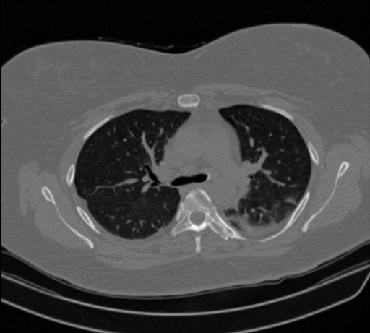

It should be mentioned that for explainability purposes [7, 8, 9], an anchor set was generated for the COV19-CT-DB database [5]. This included 11 anchors, each representing a respective 3-D CT scan obtained through an appropriate clustering procedure. Figure 2 shows a series of slices from a COVID-19 case, whereas Figure 3 shows a series of slices from a non COVID-19 case.